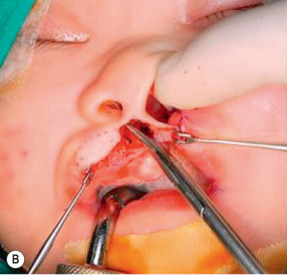

After the above markings are made, a Mohler rotation incision line is marked as a curving line from cleft side Cupid’s bow (CPHL) going upward into the base of columella and then turning back to the nasolabial junction of the non-cleft side philtral column ( Fig. 11.6 ) .

Figure 11.6

Preoperative marking: CPHR, IS, CPHL, CPHL′ and CHL, as described in Fig. 11.5 . The C-flap (C) and C-flap mucosa (CM) are marked. The dotted line on the lip is the red line, which is the junction between vermillion and mucosa. Incision lines are shown on the lip extending from point CPHL lateral to the columella on the skin edge overlying the premaxilla extending superiorly along the junction line of columella skin and septal cartilage mucosa. The cleft-side base of the philtral column is also marked (CPHL′). The proposed incision lines are marked with the rotation incision in a Mohler fashion. A small triangular white skin roll flap is designed above the CPHL′.

- ▪

The height of this rotation incision should be the same as the height of the non-cleft side philtral column.

The angle of the back cut is dependent on the width of columella.

If the columella is wide, a wider angle can be made.

The incision across the free border of the lip at CPHL should be at right angles to the axis of the white skin roll to facilitate subsequent lip closure.